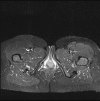

Figure 2

An axial T-2 weighted sequence with fat-saturation (TE 32 ms TR 3500) which demonstrates no residual signal abnormality on follow-up 10 months later.